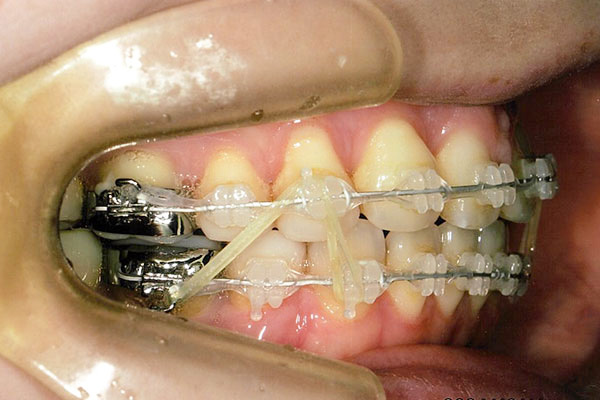

6ヶ月後

1年3ヶ月後

1年6ヶ月後

2年1ヶ月後

2年6ヶ月後